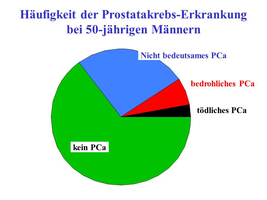

Ja, denn in Europa werden jährlich geschätzte 2,6 Millionen neue Prostatakarzinomfälle diagnostiziert. Das Robert-Koch-Institut (RKI) geht davon aus, dass allein in Deutschland ca. 67.000 Neuerkrankungen im Jahr 2012 festgestellt werden. Allerdings ist nicht jedes Vorhandensein von einzelnen wenigen Prostatakrebszellen bedrohlich. Nur ein Teil der Männer mit Prostatakrebs erkranken tatsächlich daran und etwa jeder 6. Mann mit Prostatakrebs verstirbt daran, so in Deutschland im Jahr 2008 etwa 12.000 Männer1. Das Prostatakarzinom ist somit für etwa 9 % aller Krebstoten verantwortlich. Dabei steigt das Vorkommen von Prostatakrebs durch die weltweit zunehmende Lebenserwartung sowie Ernährungs- und Umweltfaktoren deutlich an.

Ja, denn in Europa werden jährlich geschätzte 2,6 Millionen neue Prostatakarzinomfälle diagnostiziert. Das Robert-Koch-Institut (RKI) geht davon aus, dass allein in Deutschland ca. 67.000 Neuerkrankungen im Jahr 2012 festgestellt werden. Allerdings ist nicht jedes Vorhandensein von einzelnen wenigen Prostatakrebszellen bedrohlich. Nur ein Teil der Männer mit Prostatakrebs erkranken tatsächlich daran und etwa jeder 6. Mann mit Prostatakrebs verstirbt daran, so in Deutschland im Jahr 2008 etwa 12.000 Männer1. Das Prostatakarzinom ist somit für etwa 9 % aller Krebstoten verantwortlich. Dabei steigt das Vorkommen von Prostatakrebs durch die weltweit zunehmende Lebenserwartung sowie Ernährungs- und Umweltfaktoren deutlich an.

1 Quelle: Robert Koch Institut 2013